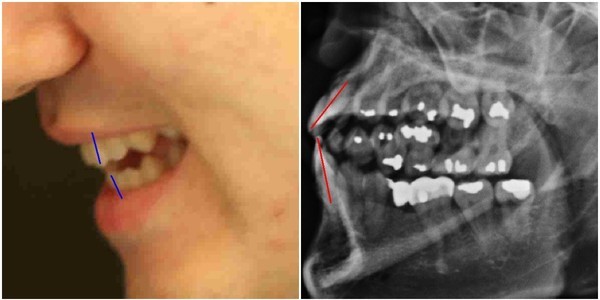

- ▲ 박원순 시장 아들 박주신씨의 치아가 보이는 실물사진(왼쪽)과 주신씨 명의의 자생병원 치아 엑스레이 사진 비교. ⓒ 뉴데일리DB

박원순 서울시장의 아들 박주신씨가 대리신검 혹은 영상자료 바꿔치기 등의 방법으로 병무청으로부터 부당하게 병역변경처분을 받았다는 의혹을 제기하다가, 공직선거법 위반(낙선목적 허위사실 유포) 혐의로 재판을 받고 있는 치과의사 김우현 원장이, 뉴데일리 <인보길초대석>을 통해, 주신씨의 구외 엑스레이(이하 치아 엑스레이) 및 주신씨의 치아 진료기록과 관련돼 강한 의문을 나타냈다.나아가 김우현 원장은 지난달 30일 열린 양승오 박사 8차 공판에서, 검찰이 사실을 왜곡한 발언을 했다며, 주신씨 치아 엑스레이 및 치과 진료기록과 관련된 검찰의 발언을 조목조목 반박했다.

김우현 원장은, “자생병원 치아 엑스레이 피사체는 주신씨가 맞다”고 주장하고 있는 치과의사 문00씨의 진술 및 그가 제출한 자료에 대해서도 신뢰하기 어렵다는 견해를 밝혔다.

피사체의 치아 상태를 볼 수 있는 자생병원 엑스레이는, 양승오 박사 재판 피고인들이 주신씨의 병역비리 의혹을 뒷받침하는 유력한 증거로 꼽고 있는 물증 가운데 하나다.

이 엑스레이는 2011년 12월 9일 자생병원에서 촬영된 것으로 알려져 있으며, 박원순 시장 측은 당시 주신씨가 허리 MRI를 촬영하면서, 함께 찍은 엑스레이라고 밝히고 있다.

반면 양승오 박사 재판 피고인들은, 자생병원 MRI는 물론 당시 함께 찍었다고 하는 문제의 엑스레이 모두 주신씨가 아닌 대리신검자의 것으로 판단하고 있다.